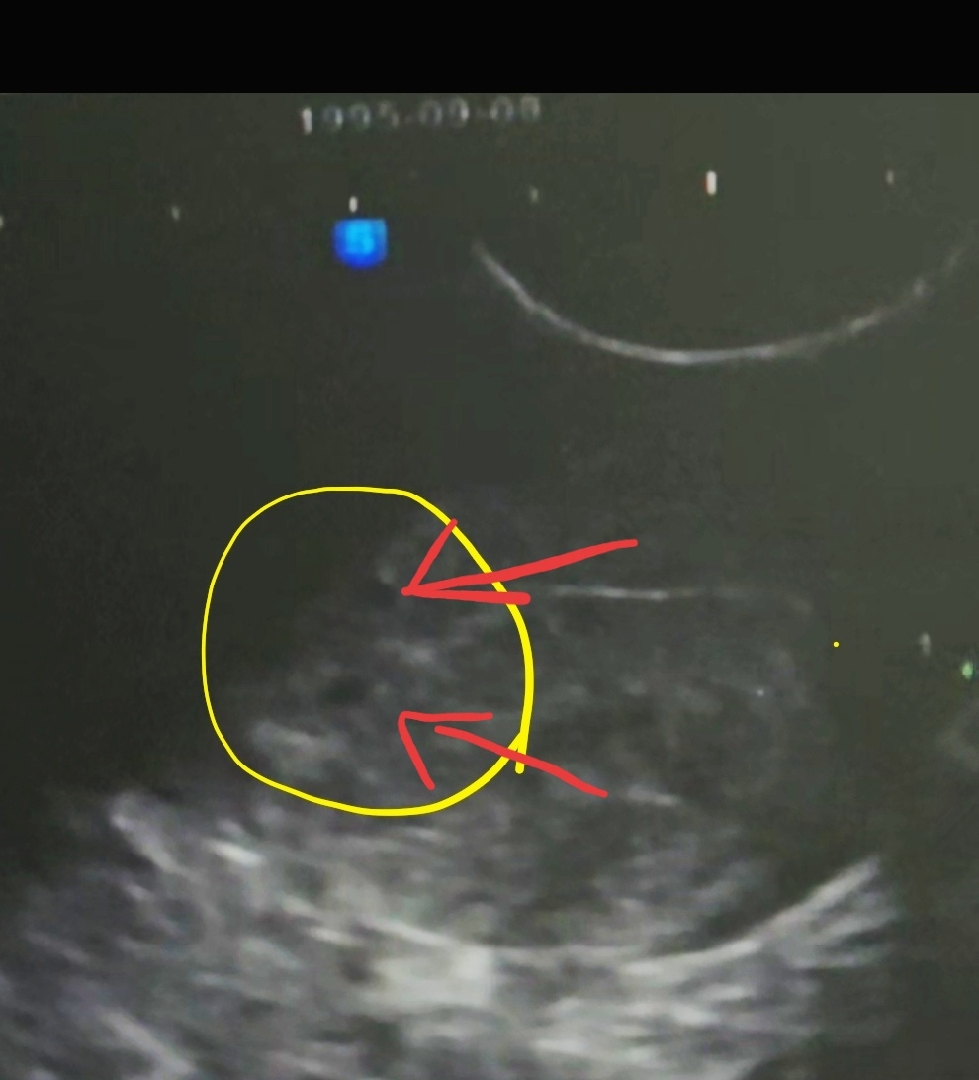

5주0일차 아기집확인! 쌍둥인거같은데...

남편이 폰으로 영상찍은거 캡쳐한건데 밑에있는게 아기집이라고 확정받았거든요! 근데 제가봣을때는 위에 똑같이 생긴게 보여서 쌍둥이 아닌가?! 했는데 의사쌤이 배란일이 좀 늦었는가 아기집이 너무 작아서 아직모른다고 다음주에 다시보자고 하시더라구요!!! (원래 주기가 한달+1주일 왓다갓다했어요!) 쌍둥이 가능성이 큰거 맞을까요..?!? 그냥 제생각이라 긴가민가한데 혹시나 싶어 기대되구....ㅋㅋㅋㅋㅋㅋㅋ 한주 또 어찌기다리죠....ㅜㅠ